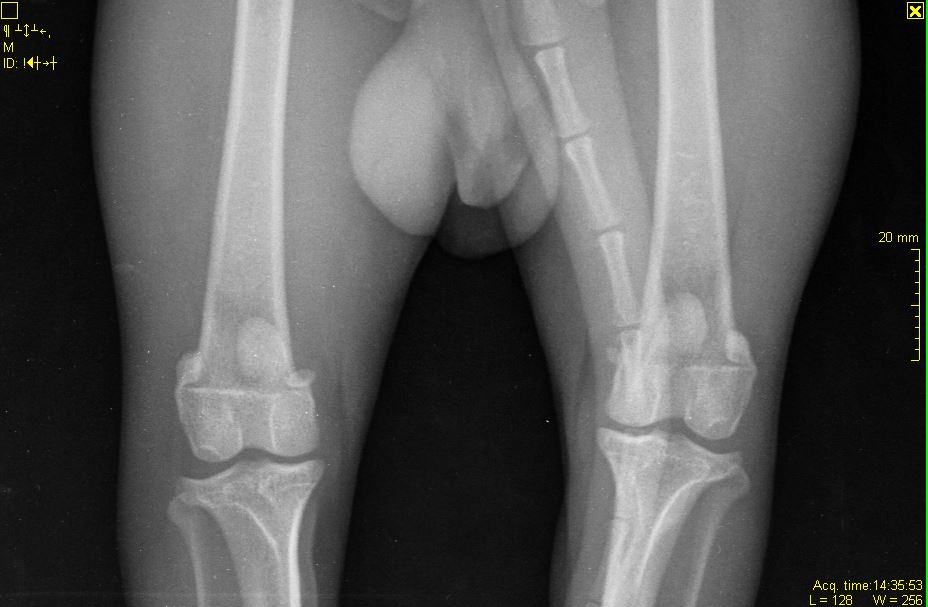

А где вы вывих тбс видите на снимках? И какой связки там нет?

А про колени вам врач ничего не говорил?

Про колени ничего не сказал совсем... хотя изначально прощупывал собаку и колени вроде как тоже проверял... А что с коленями?

Если врач реально сказал то, что вы пишете - сходите к другому и проверьте колени (хотя по снимку и так видно)

По сабжу. Переделывайте рентген - собака лежит как черти что. Должна лежать прямо. Конечности должны быть строго параллельны, рентген ТБС делается с оттяжкой. Тогда можно будет говорить о корректных снимках (и только о них). О каких связках речь, если они на рентгене не видны? Для того, чтобы разглядеть связки вообще - делают КТ либо МРТ.

И да. Согласна с Iriska - проверьте коленки. Особенно как раз правую.

Iriska, скажите, пожалуйста, что именно вы видите на снимке по коленям? Какие отклонения?

При данных проблемах собака ведет себя примерно также, как я описывала выше?

именно вывих, но коленной чашечки.

Даже при этой раскладке явно видно, что вывиха тбс нет.